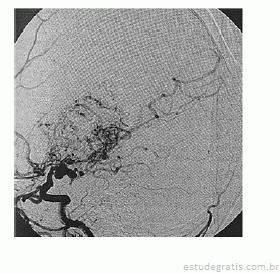

Paciente de 16 anos de idade, do sexo feminino, de asscendência japonesa, com deficits neurológicos progressivos iniciados ainda na infância, tem diagnóstico prévio de anemia falciforme. Realizou exame complementar de imagem do encéfalo, apresentado na reprodução acima. Há suspeita de doença de Moyamoya.

O exame de imagem trata-se de angiorressonância magnética de encéfalo.Comentários